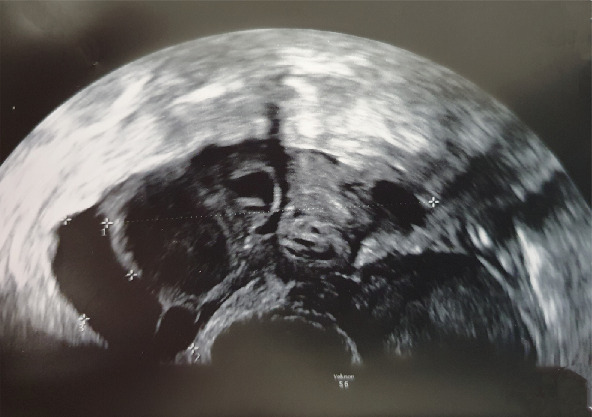

导言:宫内人工授精是辅助生殖的基本方法。它能使精子在子宫腔内直接沉积。并发症是罕见的。多胎妊娠或卵巢过度刺激可发生时,同时进行促排卵。人工突破宫颈屏障导致盆腔炎的风险很低,但可能造成的后果很严重。病例介绍:我们提出一个病例复发盆腔炎后,连续宫内人工授精。讨论盆腔炎的病理生理及治疗方法。结论:宫内节育器的炎症并发症是罕见的,但可能对生育能力的影响是毁灭性的。预防盆腔炎并及时诊断和个体化治疗应确保保持生育能力。

Introduction: Intrauterine insemination is a basic method of assisted reproduction. It enables direct deposition of sperm inside the uterine cavity. The complications are rare. Multiple pregnancy or ovarian hyperstimulation can occur when concomitant ovulation induction is performed. The risk of pelvic inflammatory disease due to the artificial cervical barrier breach is very low, but the possible consequences are serious. Case presentation: We present a case of recurrent pelvic inflammatory disease following consecutive intrauterine inseminations. Pelvic inflammatory disease pathophysiology and treatment approaches are discussed. Conclusion: Inflammatory complications of the IUI are rare, but the possible impact on fertility can be devastating. Prevention of the PID together with prompt diagnosis and individualized therapy should be assured to preserve fertility.